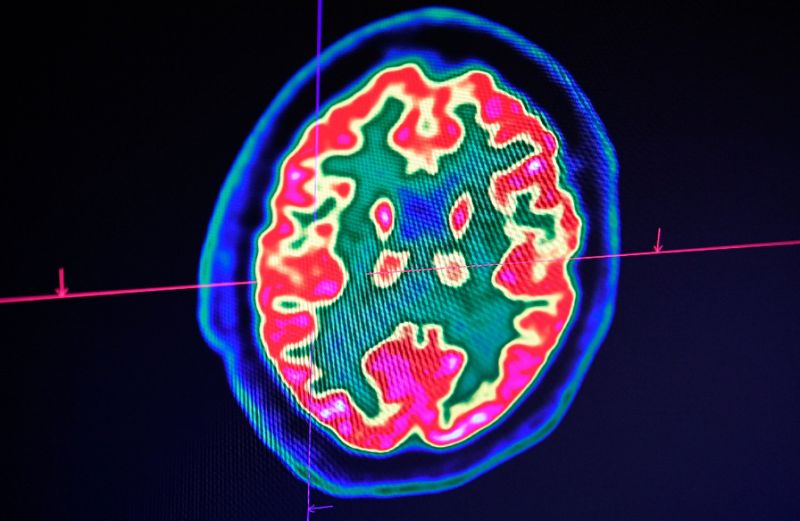

| Frankenswine: Experts said the study threw into question at what point an animal, or even humans, are dead (AFP Photo/Damien MEYER) |

Paris (AFP) - Scientists have managed to restore cell function in the brains of pigs hours after they died, in a breakthrough Wednesday that experts said threw into question the very notion of what makes animals -- or even humans -- alive.

The

findings suggest that brain cells and arteries remain functional for hours

after death (AFP Photo/Fred TANNEAU)